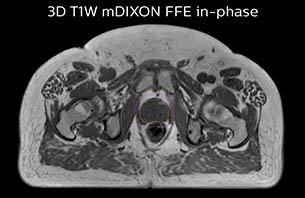

A 77-year-old male with prostate cancer cT3aN0M0, Gleason 8 and PSA 52 μg/L referred to androgen deprivation and radiation therapy with a prescribed dose of 50 Gy to the pelvic lymph node regions and 76 Gy to the prostate.

The 3D T1W FFE mDIXON sequence provides in-phase, water and fat images in one acquisition. Target and organs-at-risk are delineated on the 3D T2W TSE images. Prostate GTV is shown in orange, PTV in purple. The 3D bFFE sequence is used by the planner to mark the position of the fiducial markers (gold anchors) and contours are transferred to the digitally reconstructed radiographs (DRRs).

Based on the 3D T1W mDIXON images, MR-based density maps (MRCAT) are automatically generated. The VMAT (Volumetric Modulated Arc Therapy) plan is generated in TPS, based on MRCAT as primary image set. During the commissioning phase, dosimetric agreement between MRCAT-based and CT-based dose plans was studied and differences in the PTV dose were found to be minimal (<1% for most patients). Average difference in PTV mean values was 0.8% over the study group (n=62).